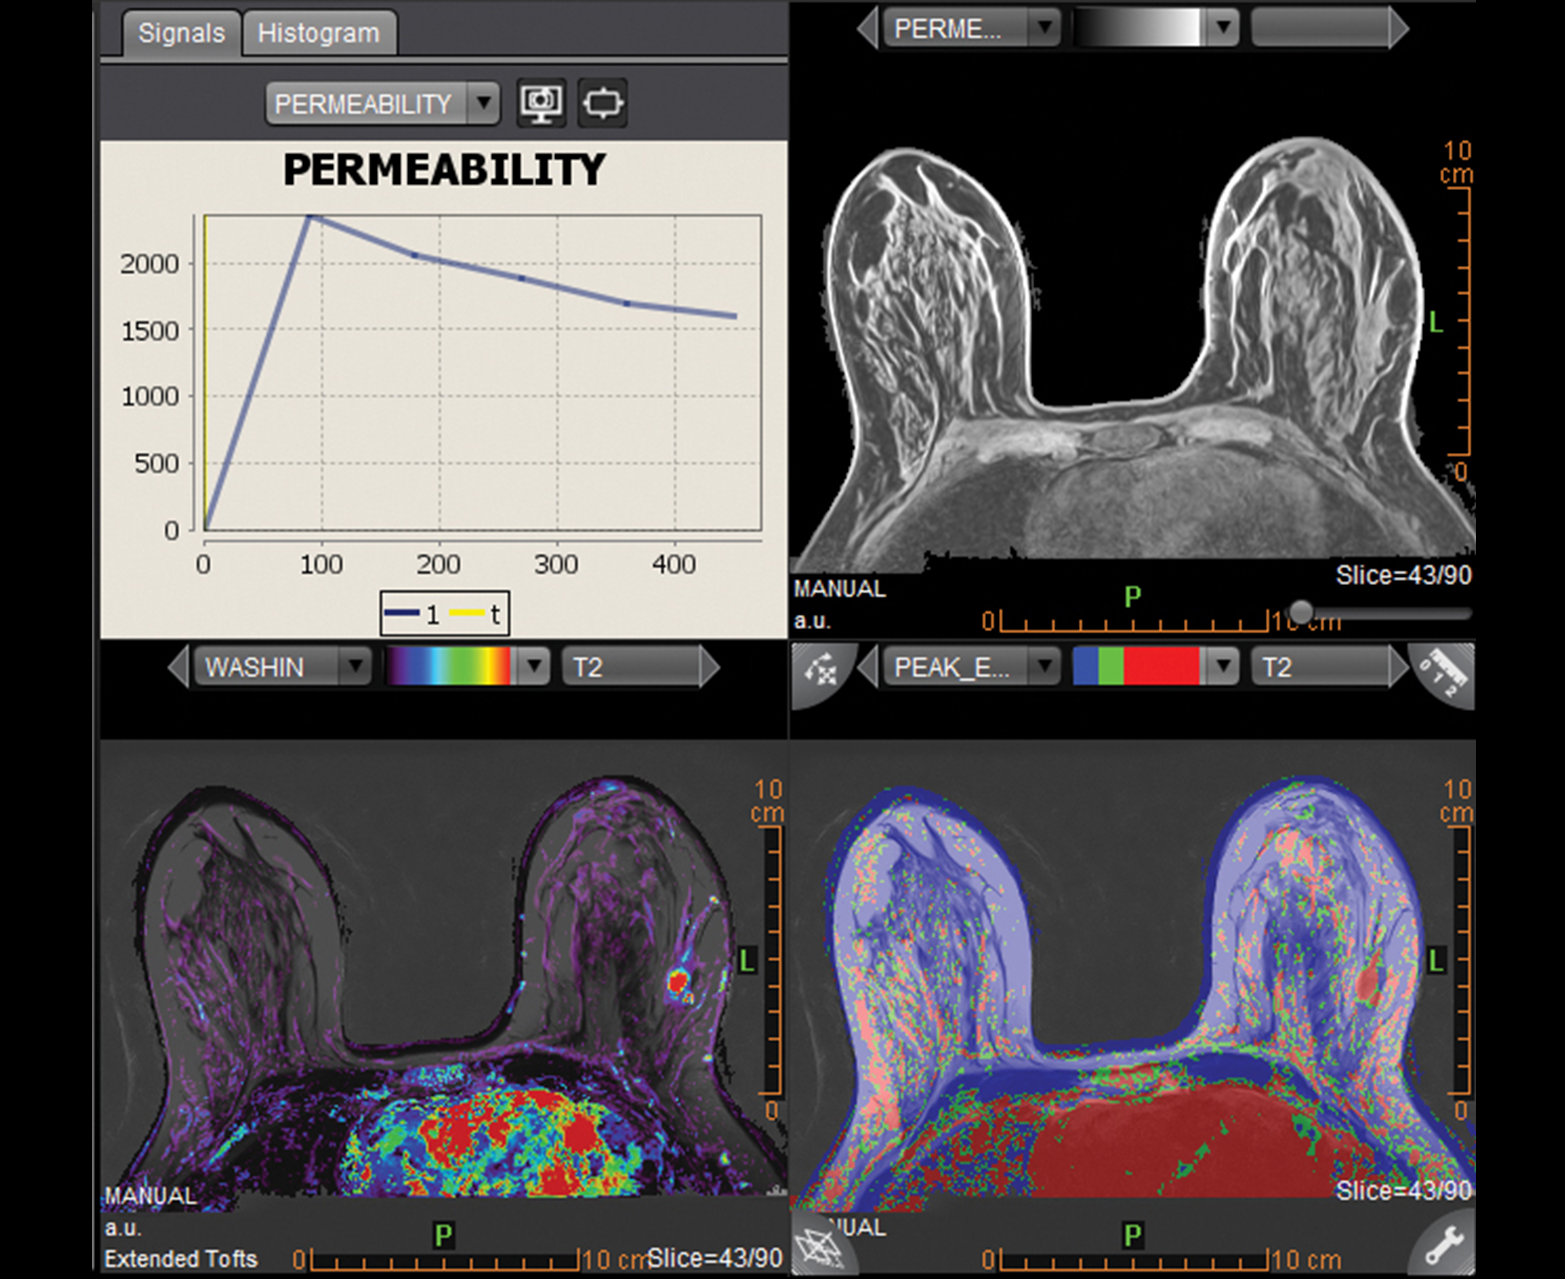

Оптимизированные решения для комплексной визуализации при патологиях груди и простаты

- Обнаружение, классификация и характеристика опухолей с быстрым доступом к качественной и количественной информации

- Интегрированные и управляемые отчеты Pi-Rad и Bi-Rads для повышения эффективности

- Автоматический расчет кинетического распределения

Многопараметрический просмотр и инструменты анализа для быстрой характеристики поражения

Интегрированная и управляемая отчетность Pi-Rads Bi-Rads